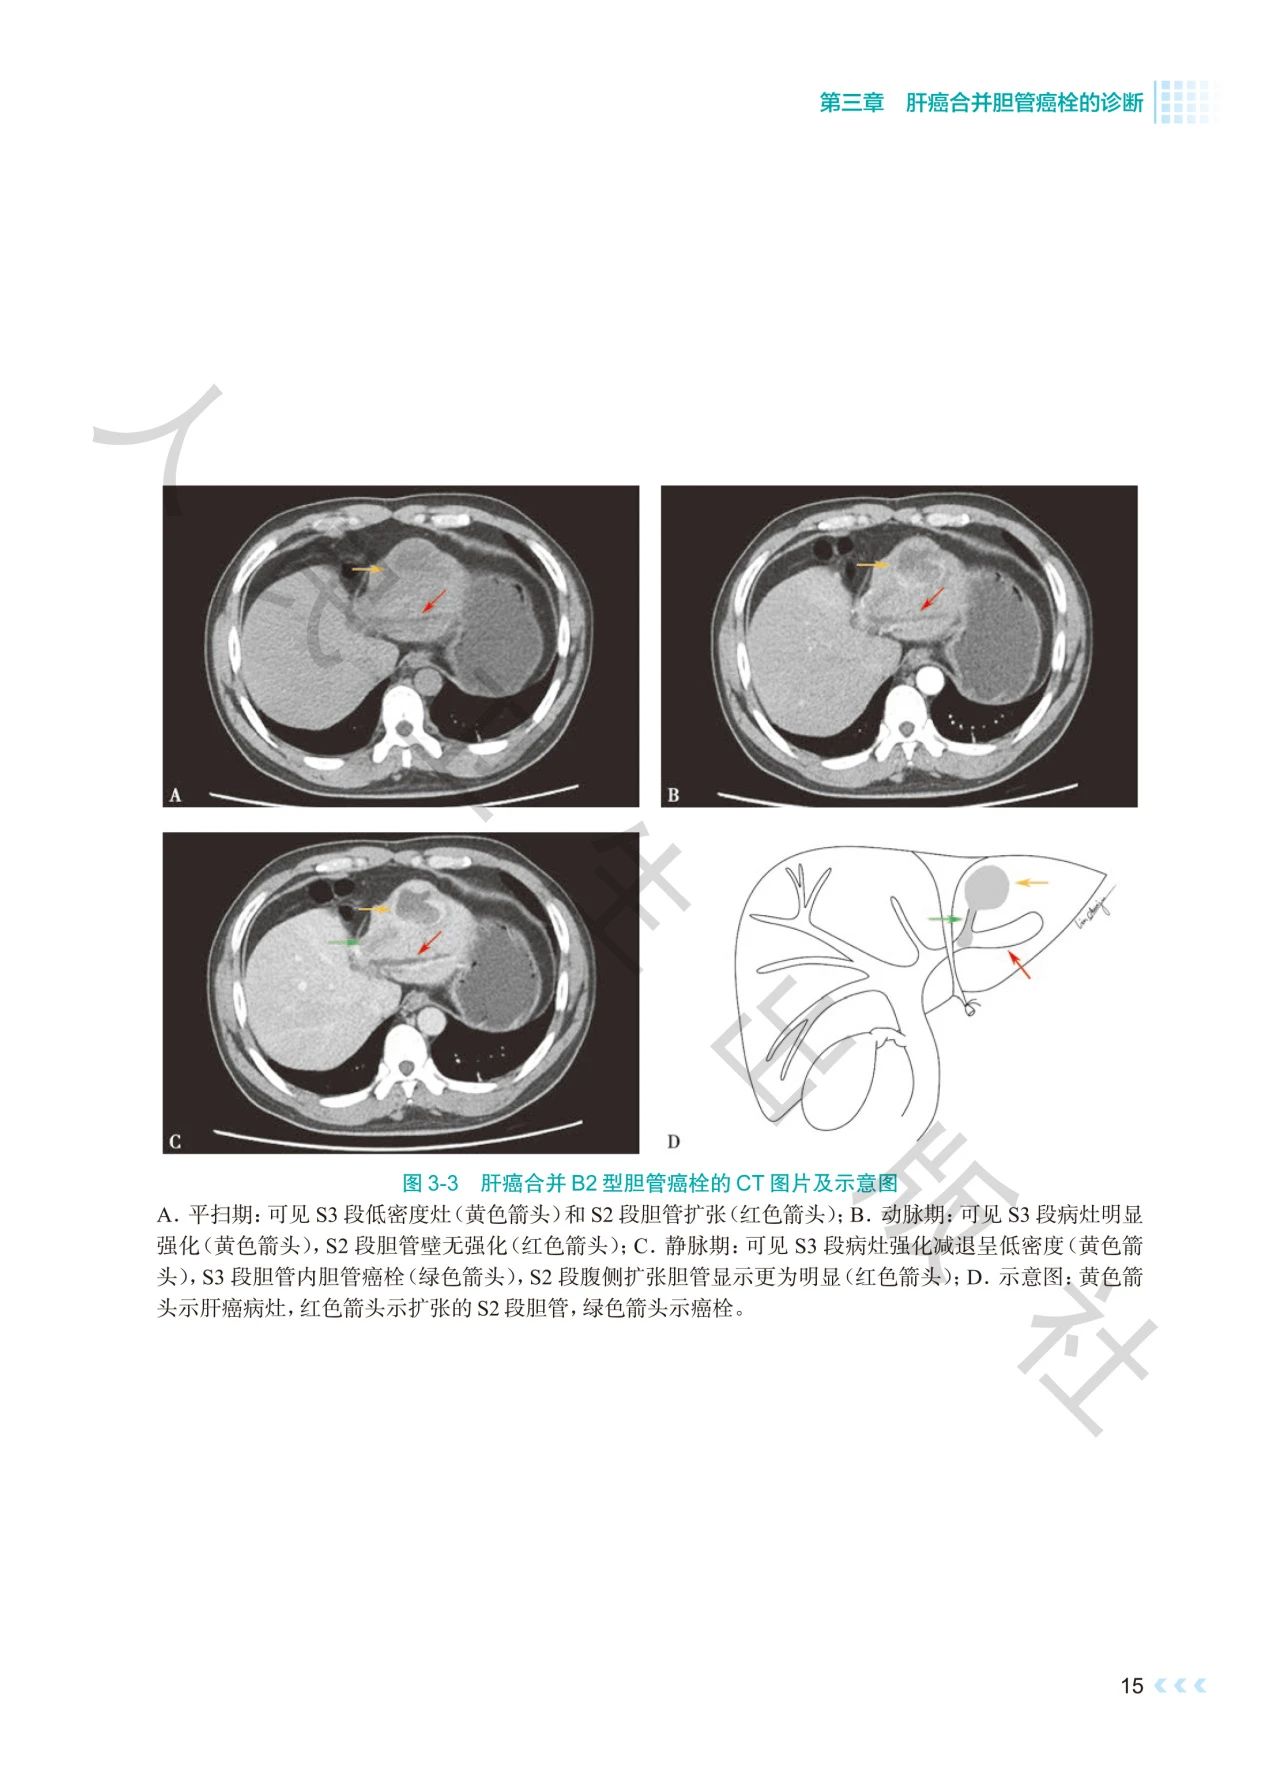

《肝癌合并胆管癌栓诊治》深入探讨了肝癌合并胆管

癌栓诊治领域的焦点问题。书中通过影像图、示意图

、手术图,详细阐述了不同分型胆管癌栓的影像学特

点及手术方式,提出q形胆总管切开取栓方法,强调解

本书通过丰富的示意图、影像图和手术图,对肝癌合

并胆管癌栓的分型、诊断策略、治疗方法等进行了深

入剖析,全面系统地总结了肝癌合并胆管癌栓领域的